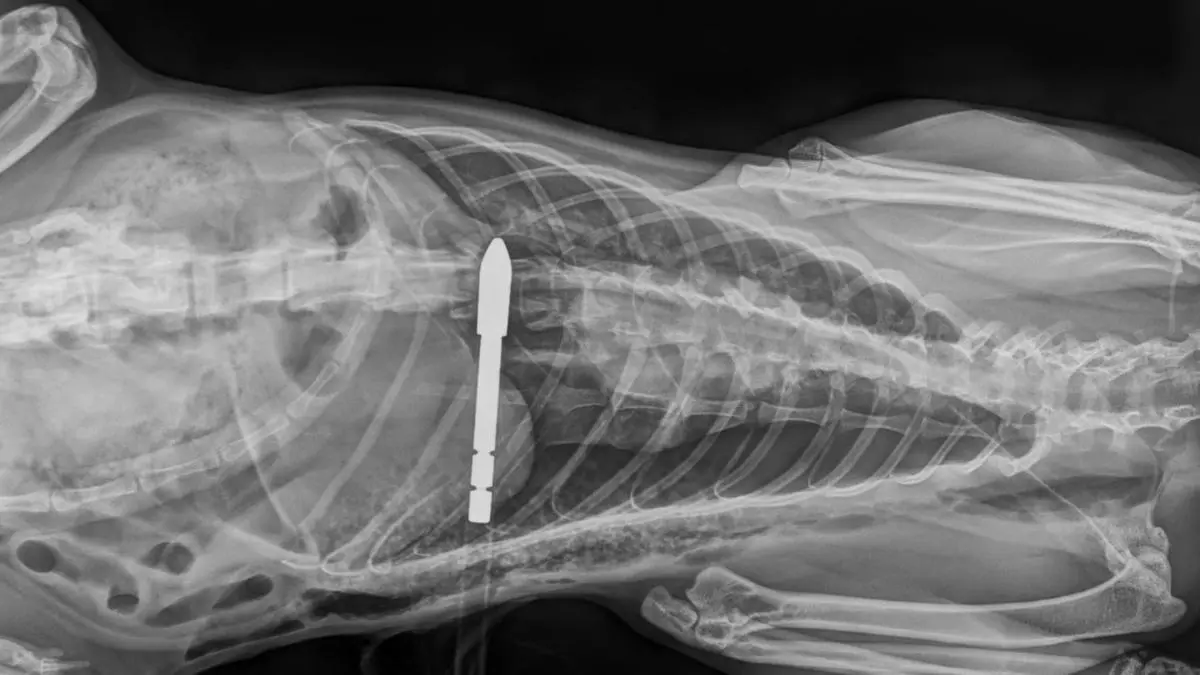

Tierquäler schoss in Zmuln bei Liebenfels mit Pfeil auf Katze

Eine freilaufende Katze wurde von einem Unbekannten mit einem Pfeil schwer verletzt. Das Tier wurde mit schweren Lungenverletzungen in eine Tierklinik gebracht. Dort kämpft sie um ihr Leben.

Das Röntgenbild zeigt die Verletzung